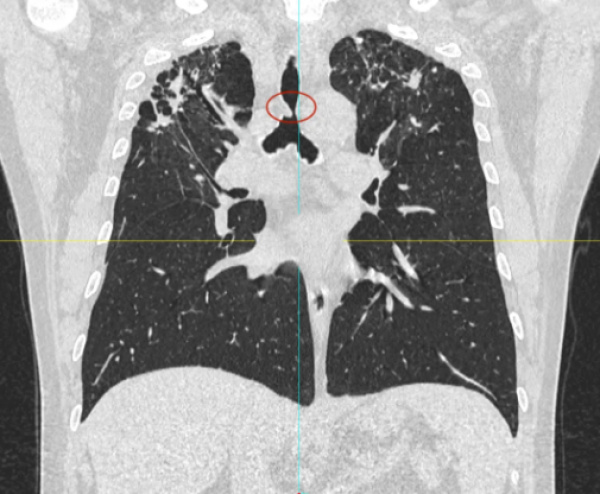

日前,患者趙先生(化名)因進(jìn)行性呼吸困難來到河南省胸科醫(yī)院尋求治療,經(jīng)檢查確診為支氣管結(jié)核導(dǎo)致氣管中下段重度瘢痕性狹窄,最窄處直徑僅約3mm,且局部軟骨環(huán)破壞、塌陷,這意味著支撐氣道的結(jié)構(gòu)遭到損毀,通氣功能嚴(yán)重受損,且因狹窄部位靠近隆突,治療操作風(fēng)險(xiǎn)極高,稍有不慎就可能導(dǎo)致大出血、氣道完全閉塞等致命并發(fā)癥。

在硬質(zhì)支氣管鏡引導(dǎo)下,手術(shù)團(tuán)隊(duì)首先對(duì)狹窄部位進(jìn)行球囊擴(kuò)張。隨后,將術(shù)前根據(jù)患者三維CT數(shù)據(jù)定制的Y型硅酮支架精準(zhǔn)覆蓋于氣管狹窄段。該支架確保與患者自身的氣道解剖結(jié)構(gòu)完美貼合,實(shí)現(xiàn)最佳支撐效果,并最大限度減少粘膜刺激增生等特點(diǎn)。支架展開后穩(wěn)定支撐于隆突及雙側(cè)主支氣管,氣道狹窄立即得到解除。

隨著手術(shù)順利完成,趙先生蘇醒后自覺呼吸順暢,術(shù)后復(fù)查顯示支架位置良好,氣道通暢,呼吸困難癥狀顯著緩解。